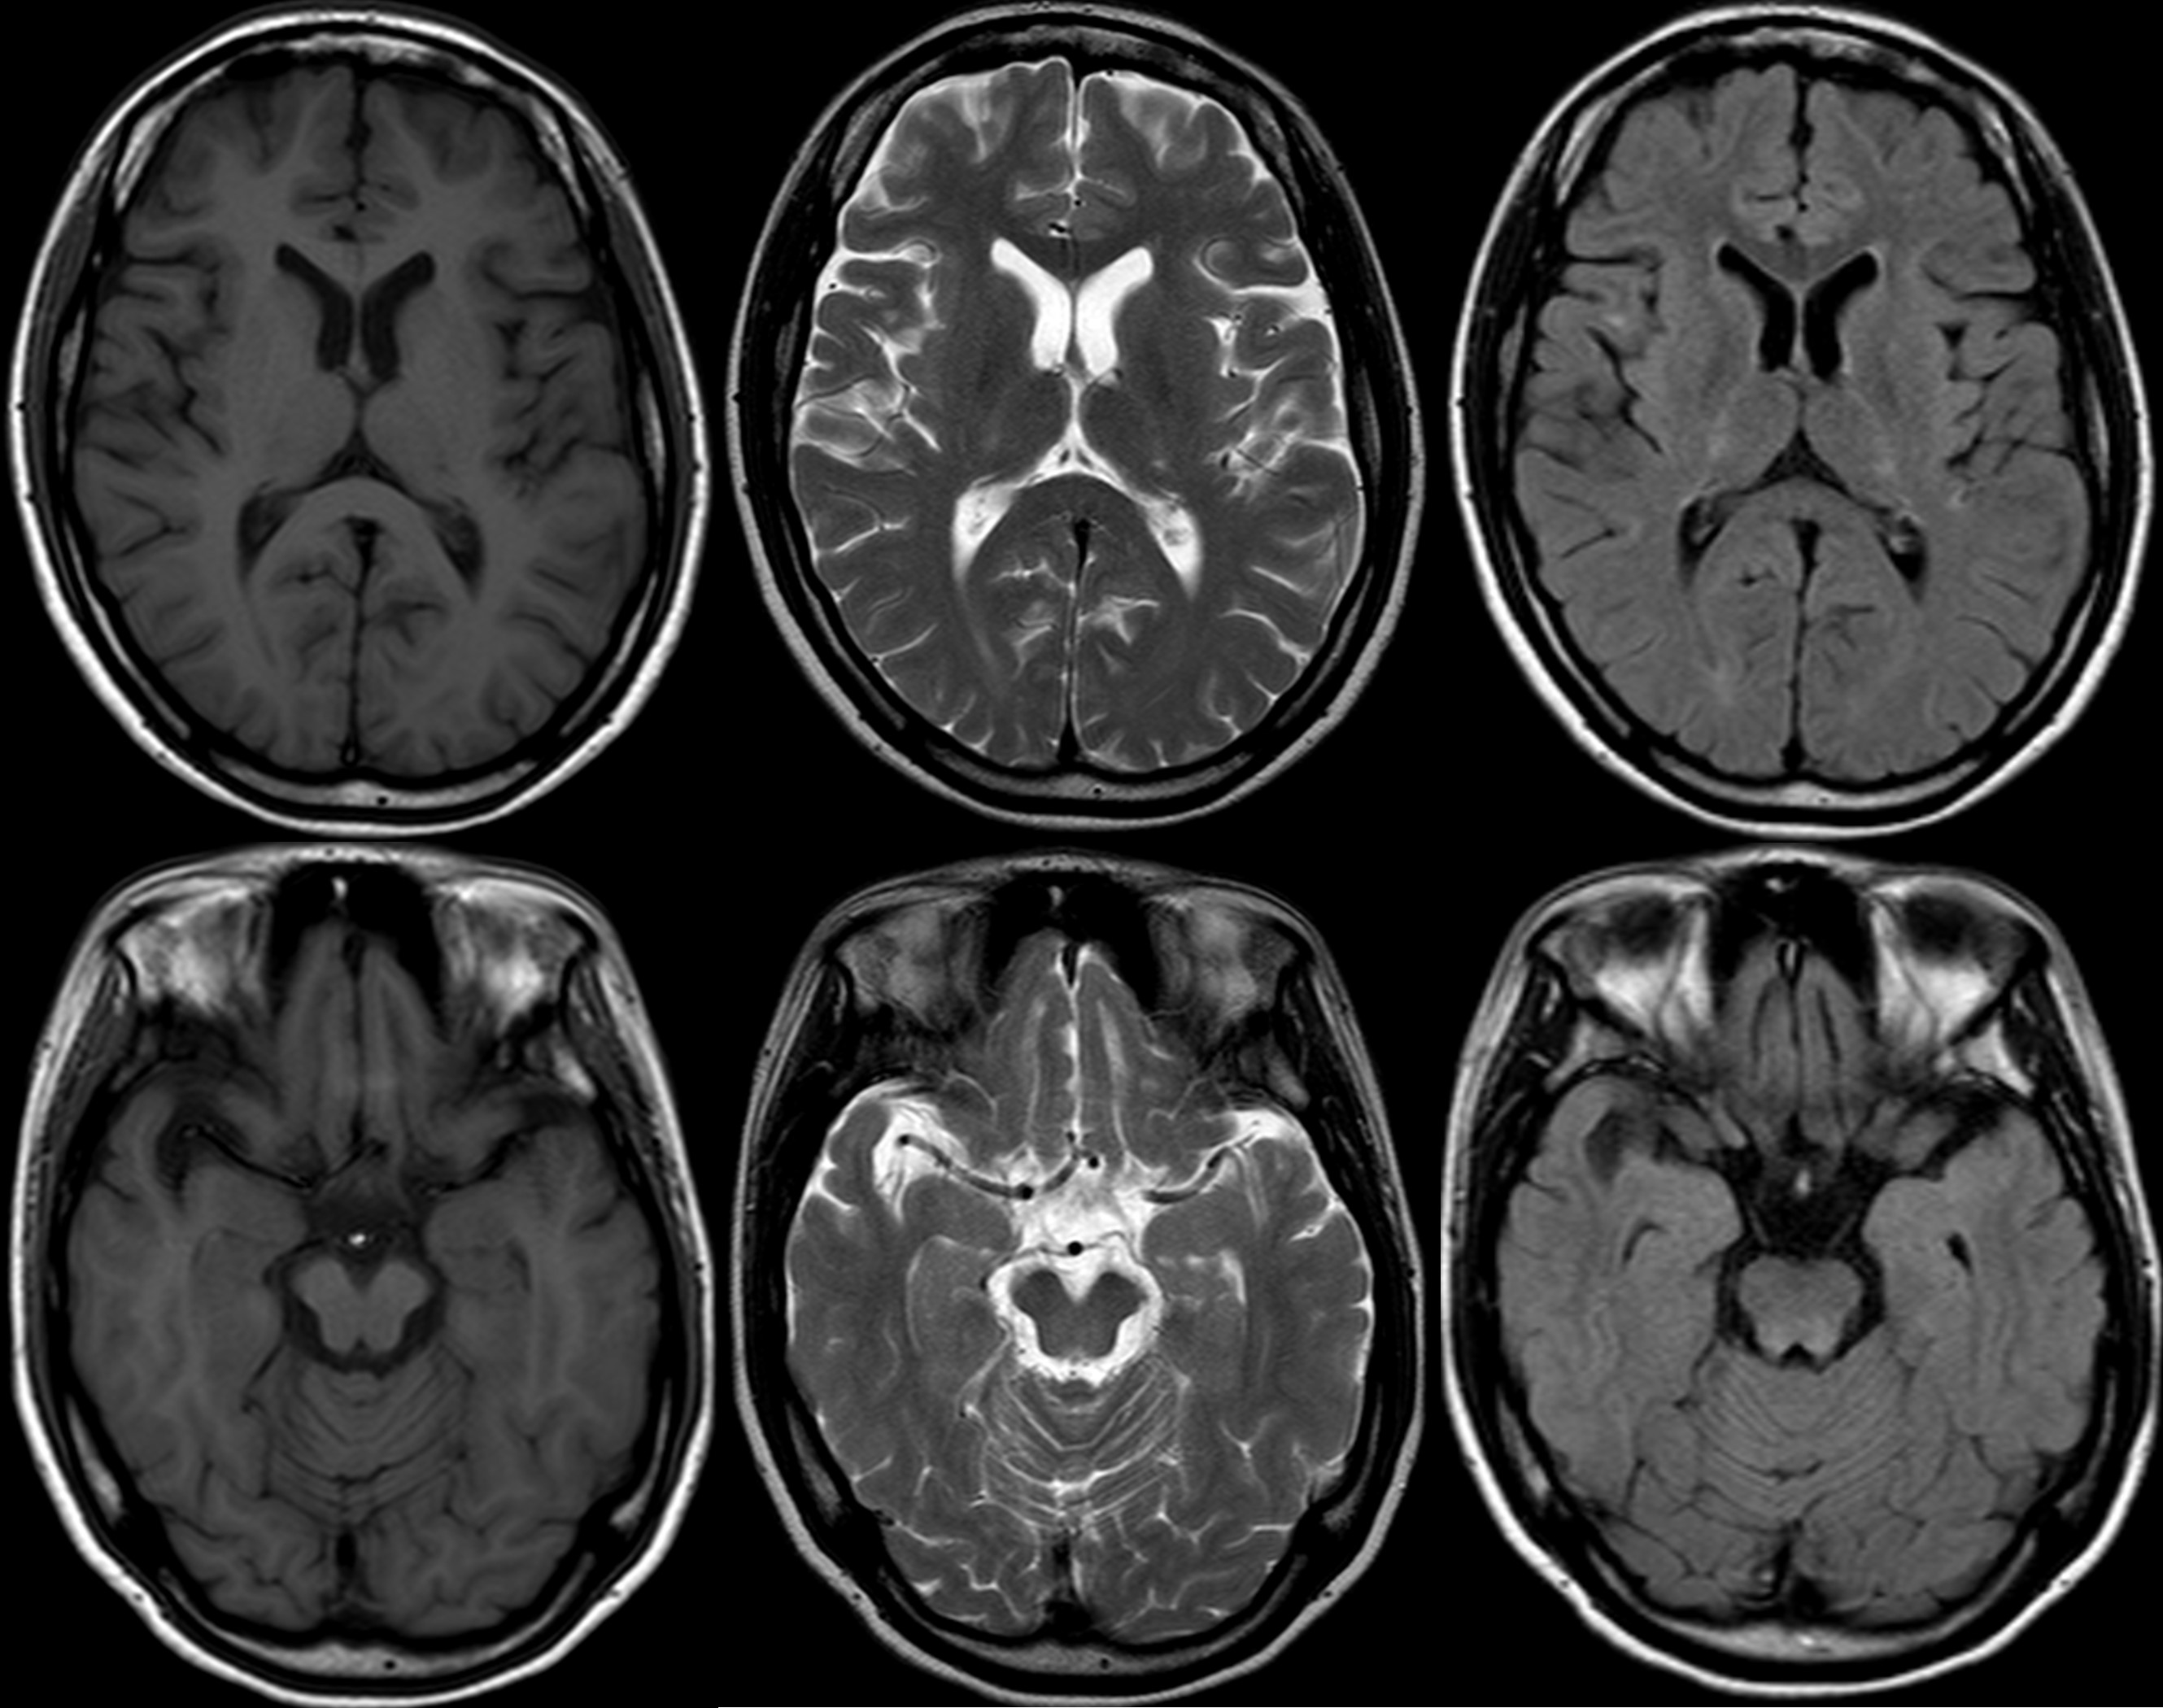

Bilateral symmetric thalamic signals in MRI

symmetric dorsal pontine signals in MRI